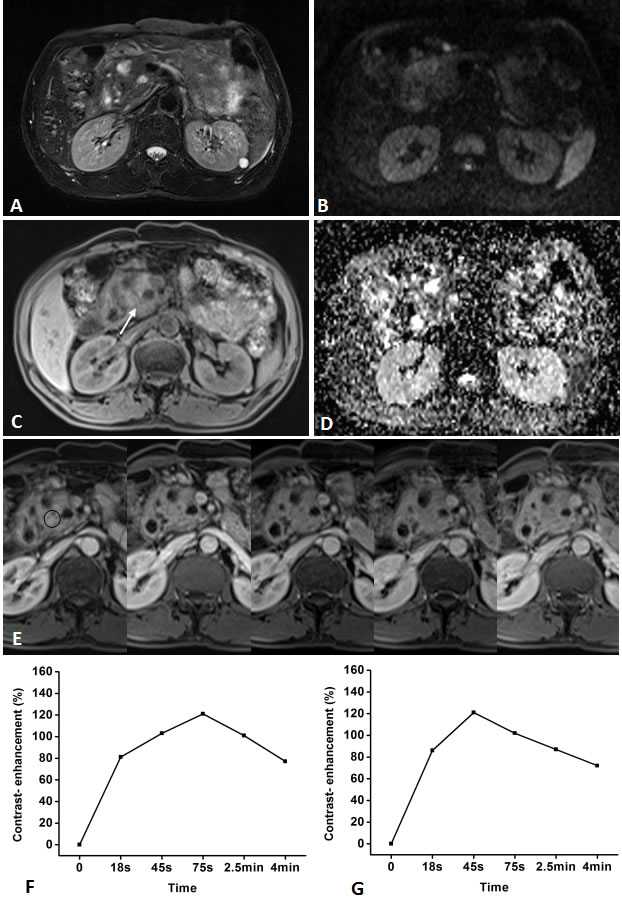

Figure 4: Representative pancreatic T2-weighted image (A), DWI with a b value of 600 s/mm2 (B), T1-weighted image (C), ADC map (D), DCE-MR images (E), and TIC profiles (F, G) in a 55-year-old man with mass-forming chronic focal pancreatitis in the head of pancreas (white arrow). DCE-MR images: 18s, 45s, 75s, 2.5 and 4min after contrast injection with constant gray scale. The ROIs of mass indicated with black circle and non-mass adjacent parenchyma (NAP) was located in pancreatic body. Pancreatic mass demonstrates type-III a TIC which shows a gradual increase followed by a more slowly decreasing enhancement pattern, while NAP demonstrates type-II a TIC which shows a relatively rapid increasing then gradually decreasing enhancement pattern. DWI shows pancreatic mass is clearly seen as isointense with ill-defined margin.